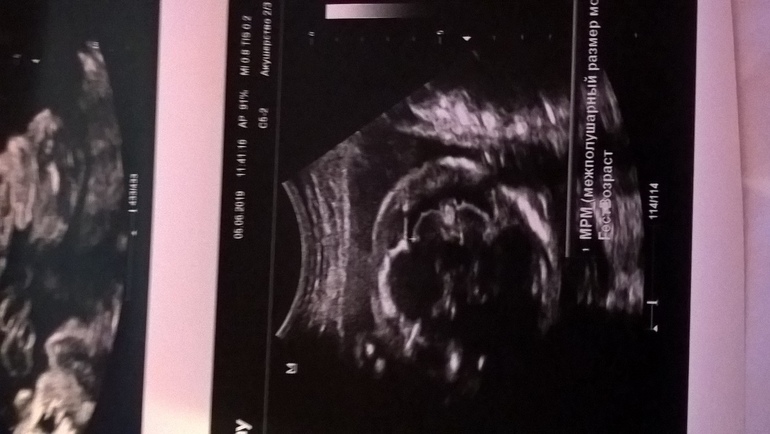

Фото УЗИ малыша

УЗИ сделавшее сюрприз, так как по нему будет мальчик, хотя раньше говорили девочка. Может кто может посмотреть фото и определить кто же все таки))